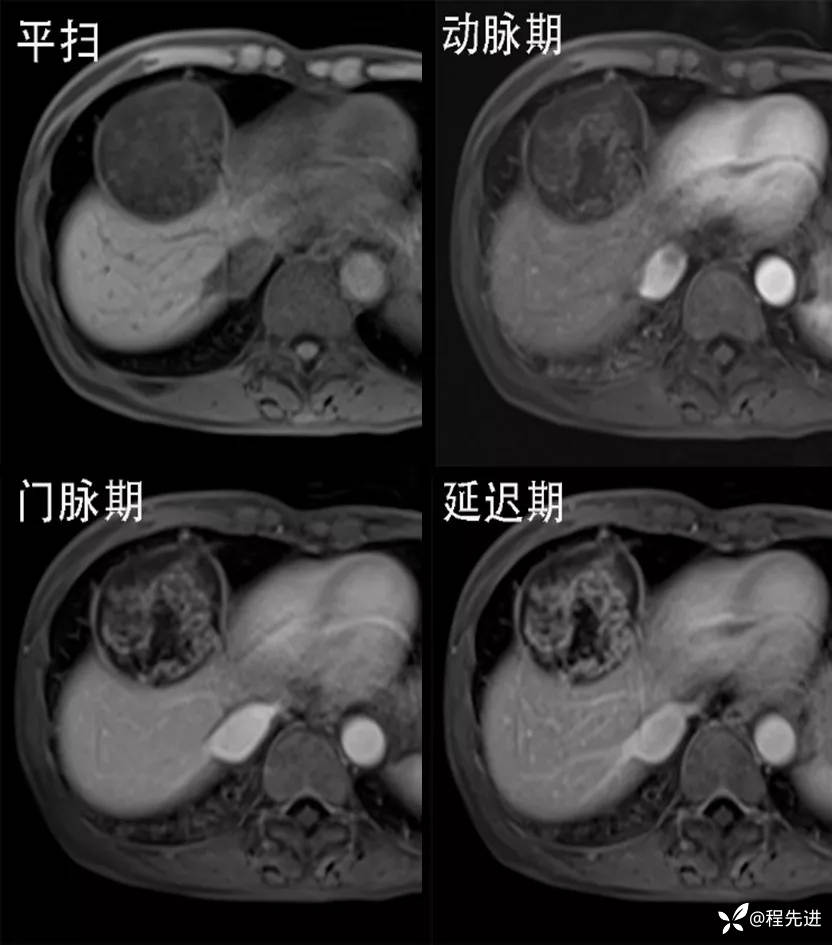

MRI平扫+增强:

img